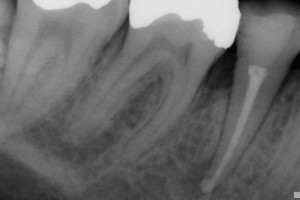

Back in Dec 2010, I wrote a blog about Pain Free Root Canal. Thing is, since that time we have had a steady stream of people walking into the surgery asking for Pain Free Root Canal. There must be lots of dentists out there doing a lot of painful root canal since that is what most people think is normal! Root canal is a very routine procedure at No9. We do lots of root treatments. I can safely say all of our root canal is pain free, that's the way it should be! So if you need root canal. Come and see us and we will fix your tooth. We wont hurt you..... and that's a promise. Pete